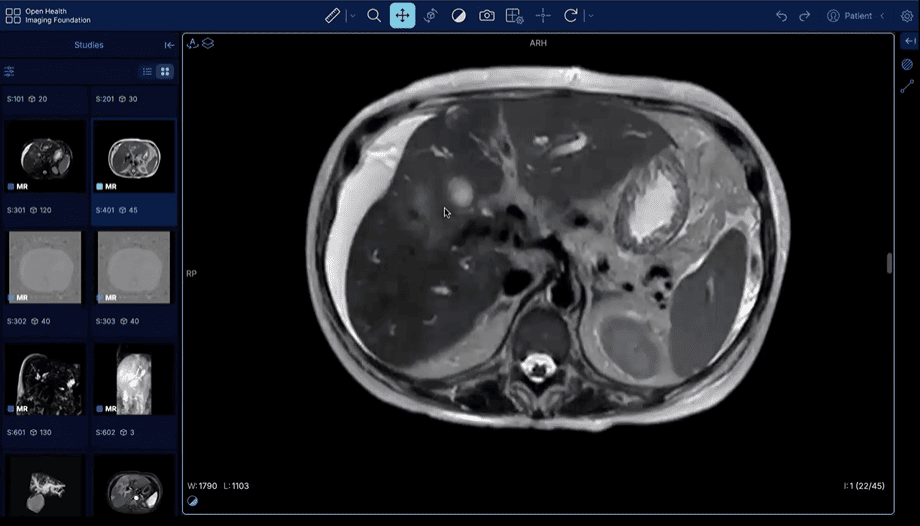

Acesse um PACS com exames reais selecionados para treinar raciocínio diagnóstico como na rotina de um grande serviço de referência.